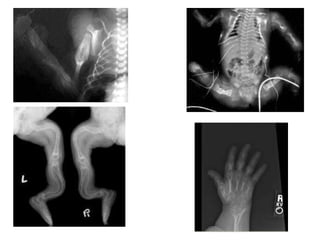

Radiographic skeletal survey after birth

 Plain radiographs :3 radiologic categories of

OI

A. Category I – Thin and gracile bones

B. Category II – Short and thick limbs

C. Category III – Cystic changes

Radiologic features

 Fractures – Commonly, transverse fractures and those

affecting the lower limbs

 Excessive callus formation and popcorn bones - Multiple

scalloped, radiolucent areas with radiodense rims

 Skull changes - Wormian bones enlargement of frontal and

mastoid sinuses, and platybasia with or without basilar

impression

 Deformities of the thoracic cage - Fractured and beaded

ribs and pectus carinatum

 Pelvic and proximal femoral changes - Narrow pelvis,

compression fractures, protrusio acetabuli, and shepherd’s-

crook deformities of the femurs

 Mild OI (type I) : thinning of the long bones with

thin cortices,wormian bones,no deformity of long

bones

 Extremely severe OI (type II) : beaded ribs, broad

bones, and numerous fractures with deformities

of long bones

 Moderate and severe OI (types III and IV) :cystic

metaphyses, or a popcorn appearance of growth

cartilage, deformities of long bones, old rib

fractures, vertebral fractures